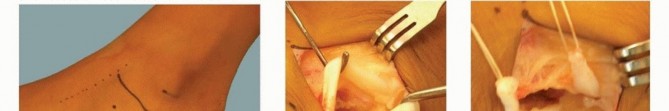

Medial Cuneiform OsteotomyAssess the forefoot for structural supination deformity by holding the heel with the ankle in neutral dorsiflexion and viewing in line with the axis of the foot from toes to heel.Visualize the plane of the metatarsal heads in relation to the long axis of the tibia ( TECH FIG 6A). Also, assess the dorsal-plantar mobility of the first metatarsal-medial cuneiform joint.A plantarflexion osteotomy of the medial forefoot-midfoot is required if the metatarsals are supinated.A plantar-based closing wedge osteotomy in the midportion of the medial cuneiform is an effective procedure to correct this deformity ( TECH FIG 6B). The plantar base of the resected wedge generally measures 4 to 7 mm in length.The osteotomy is closed and internally fixed with a 0.062-inch smooth wire staple inserted from plantar to dorsal.Check to ensure correction of the forefoot deformity ( TECH FIG 6C).

| TECH FIG 6 • A. The rotational alignment of the forefoot is assessed after correction of the hindfoot deformity and the heel cord contracture. If, as in this case, the forefoot is supinated, an osteotomy of the forefoot is required. B. A medial cuneiform plantar-based closing wedge osteotomy will correct the supination deformity of the forefoot. C. Forefoot deformity has been corrected. (From Mosca VS. Calcaneal lengthening osteotomy for valgus deformity of the hindfoot. In: Tolo V, Skaggs D, eds. Master Techniques in Orthopaedic Surgery: Pediatric Orthopaedics. Philadelphia: Lippincott Williams & Wilkins, 2008:263-276.)